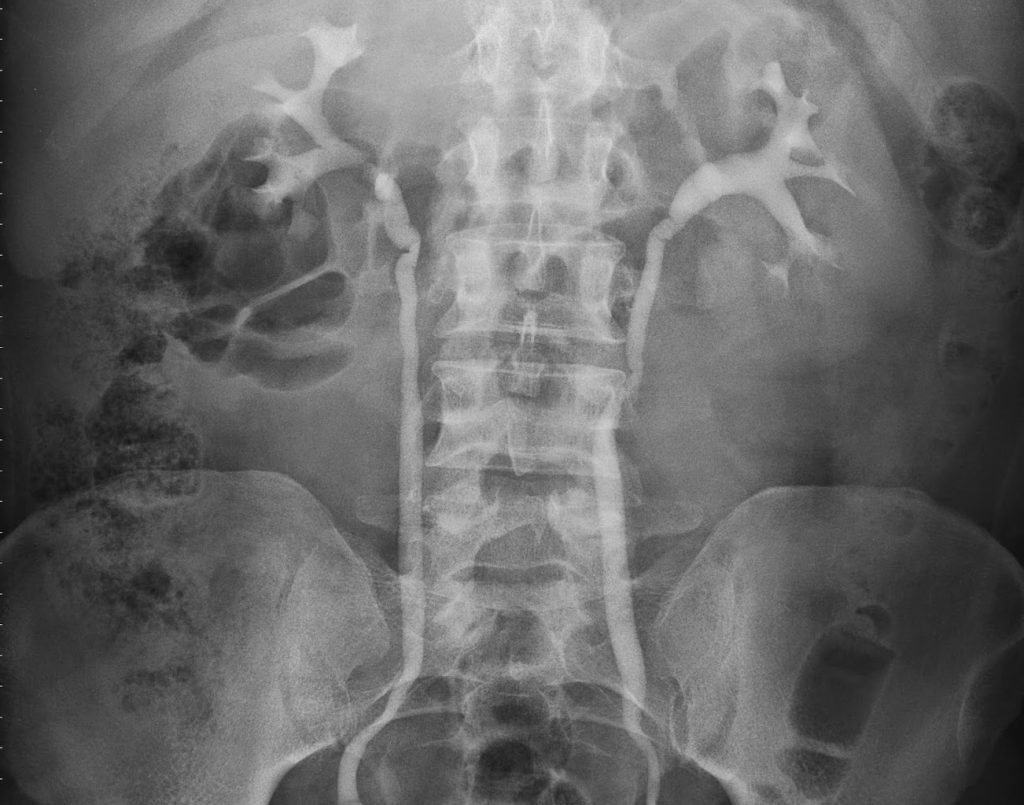

پیلوگرام رتروگراد برای سنگ کلیه